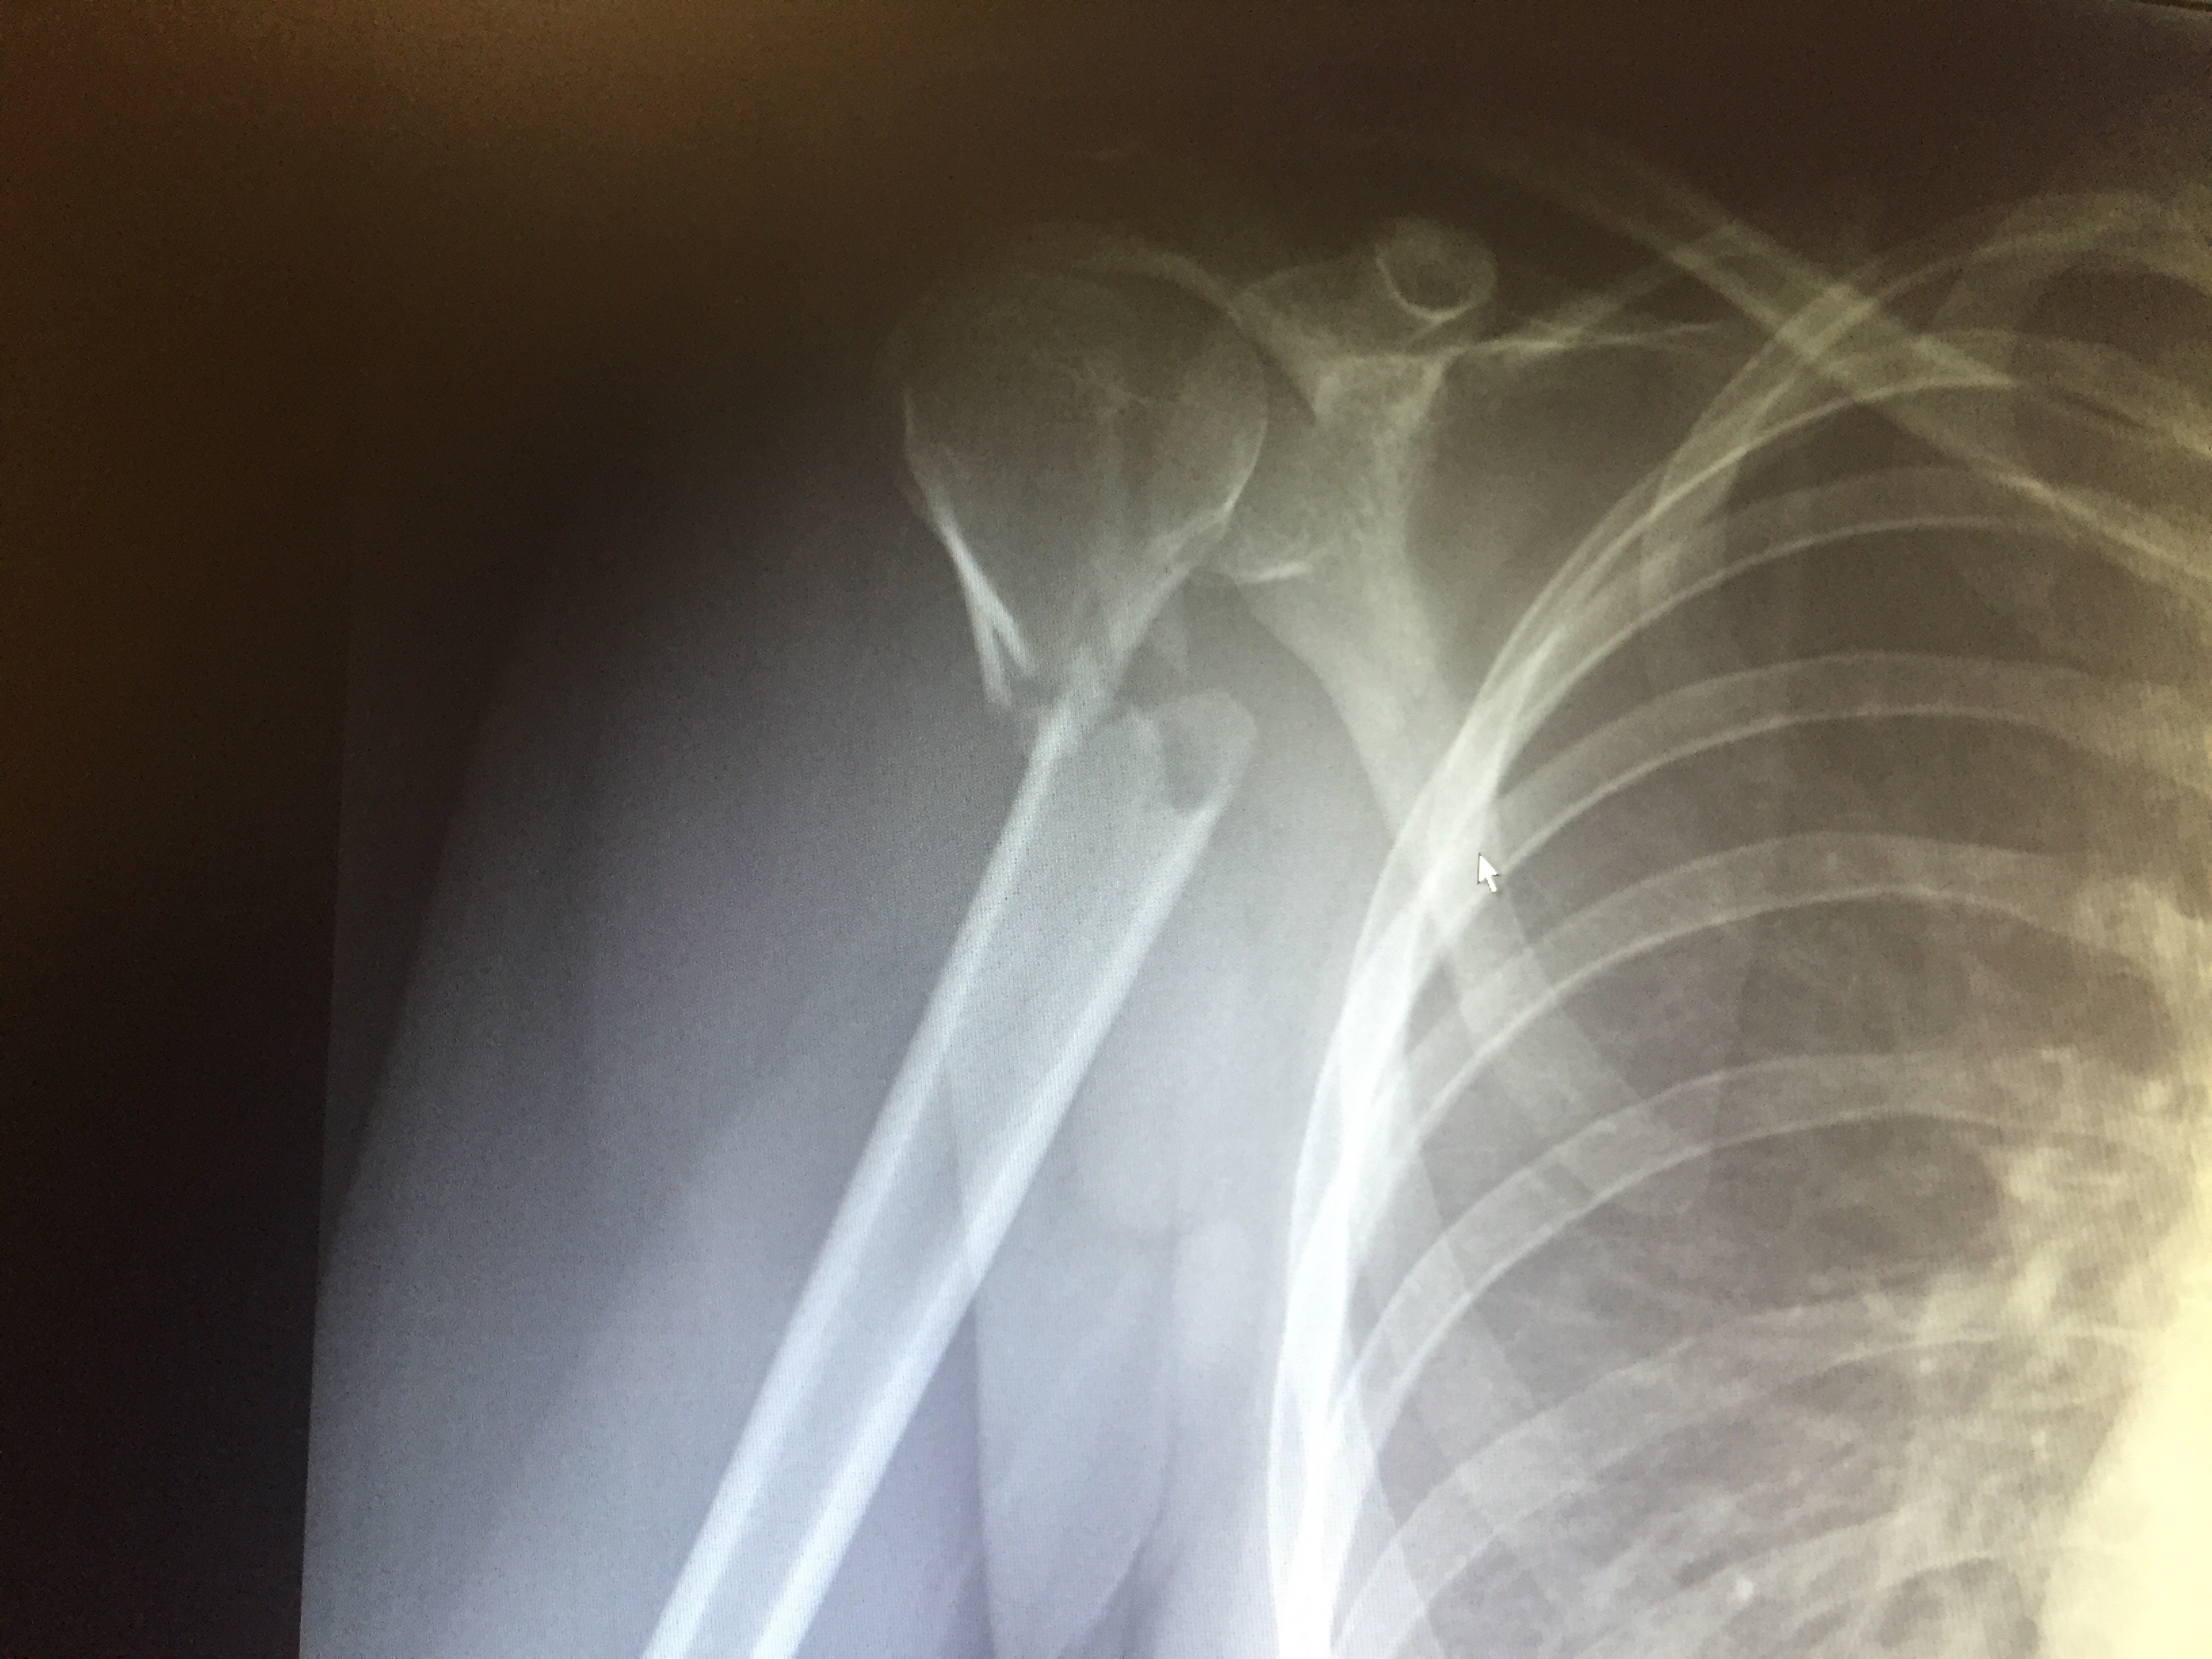

1. That X-ray looks horrific! So it all happened in Whistler? I prefer walking up there, though. Jersey sounds good, though. Also, I’d love to *walk* the North Downs Way. I only know the Kentish end and Wye is absolutely beautiful. My parents and granddad used to take me there as a child to enjoy a walk, a picnic and hills (there aren’t many in East Kent). I once got out of school gym class because I’d been walking in the hills near Wye and I couldn’t walk the next day. I wasn’t as fit back then, but I don’t envy you running there. Except in the sense of ‘I wish I was fit enough to run there’. Your goals all seem pretty ambitious. Hope you make them all. I’m not sure if I’m running at all this year. The gym, yes. Running, no. Maybe soon. Maybe not.

1. Yeah Whistler vs Shoulder was only going to have one winner! Shamefully never been on the NDW but excited to try it. Although slightly scared that after your story! You should definitely visit Jersey!!